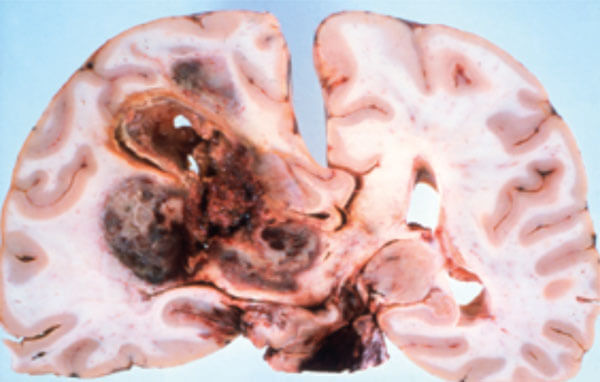

Figure 2: Pathology of large convexity meningioma compressing the brain with intrinsic haemorrhage.

Meningiomas arising from the tuberculum sellae cause early compression of the optic nerves or chiasma and can be mistaken clinically for a pituitary tumour or aneurysm. Meningiomas arising from the peripheral meninges grow slowly indent, compress the adjacent brain as seen in Figure 2, and if arising in the parietal or occipital areas may present with homonymous visual field defects. We also encounter patients with large frontal meningiomas originating from the falx, crista galli or olfactory groove (Figure 3) presenting to the eye clinic with headache and minimal general symptoms, but in most of such cases papilloedema will be present leading to the diagnosis.

Figure 5: Pathology of an infiltrating glioblastoma with extensive haemorrhage.

Astrocytomas comprise up to 50% of primary brain tumours and can originate anywhere in the brain parenchyma, often presenting with seizures; the more benign varieties are commonest in the fourth decade of life but the GBM is usually seen in the fifth or sixth decade (Figures 4 and 5).